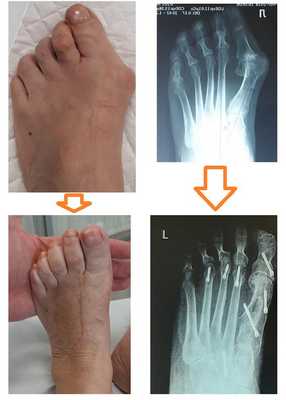

При более сильно выраженной деформации используется остеотомия первой плюсневой кости и основной фаланги 1 пальца. Ниже приведён клинический пример Z-образной или Scarf остеотомии 1 плюсневой кости и клиновидной варизующей или Akin остеотомии основной фаланги 1 пальца.

В том случае, если деформация затрагивает 2 и более пальца то необходима более сложная операция, затрагивающая сразу несколько плюсневых костей и фаланг а также включающая вмешательство на мягких тканях. Ниже приведён пример реконструкции переднего отдела стопы при запущенной деформации, включающий Z-образную остеотомию 1 плюсневой кости и клиновидную варизующюю остеотомию основной фаланги 1 пальца, артропластическую резекцию 2-3-4 проксимальных межфаланговых суставов, шевронную остеотомию 5 плюсневой кости.

Сроки реабилитации варьируют в зависимости от проведенной операции, чем больше объём вмешательства, тем больше времени потребуется на восстановление.